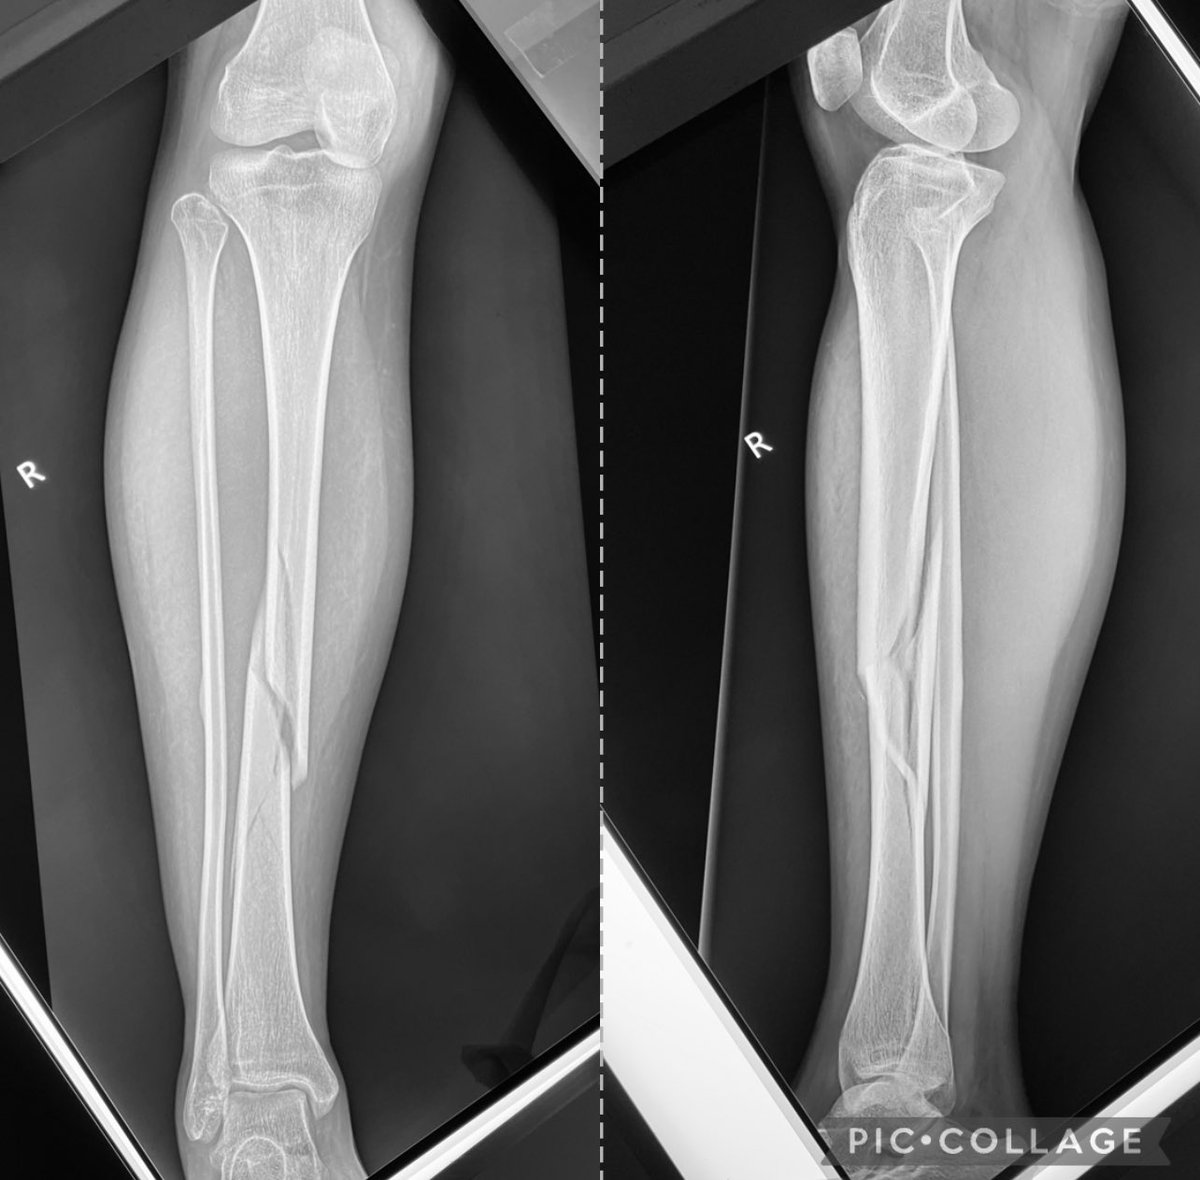

Closed Reduction, Application of Long Leg Cast for Closed Comminuted Diaphyseal Fracture (Middle Third) of the Right Tibia (25/F, Motorcycle accident)

Antonio Tanchuling Jr. M.D. tweet mediaAntonio Tanchuling Jr. M.D. tweet mediaAntonio Tanchuling Jr. M.D. tweet media

@nongtanch I think is better to operate with a nail. Soft tissues control, less ankle and knee stiffness, and avoid rotational secundary displacement, usually in external rotation and early weightbearing

@nongtanch Proximal fibula is also broken and is more expensive for the patient not to work in 4 months, maybe